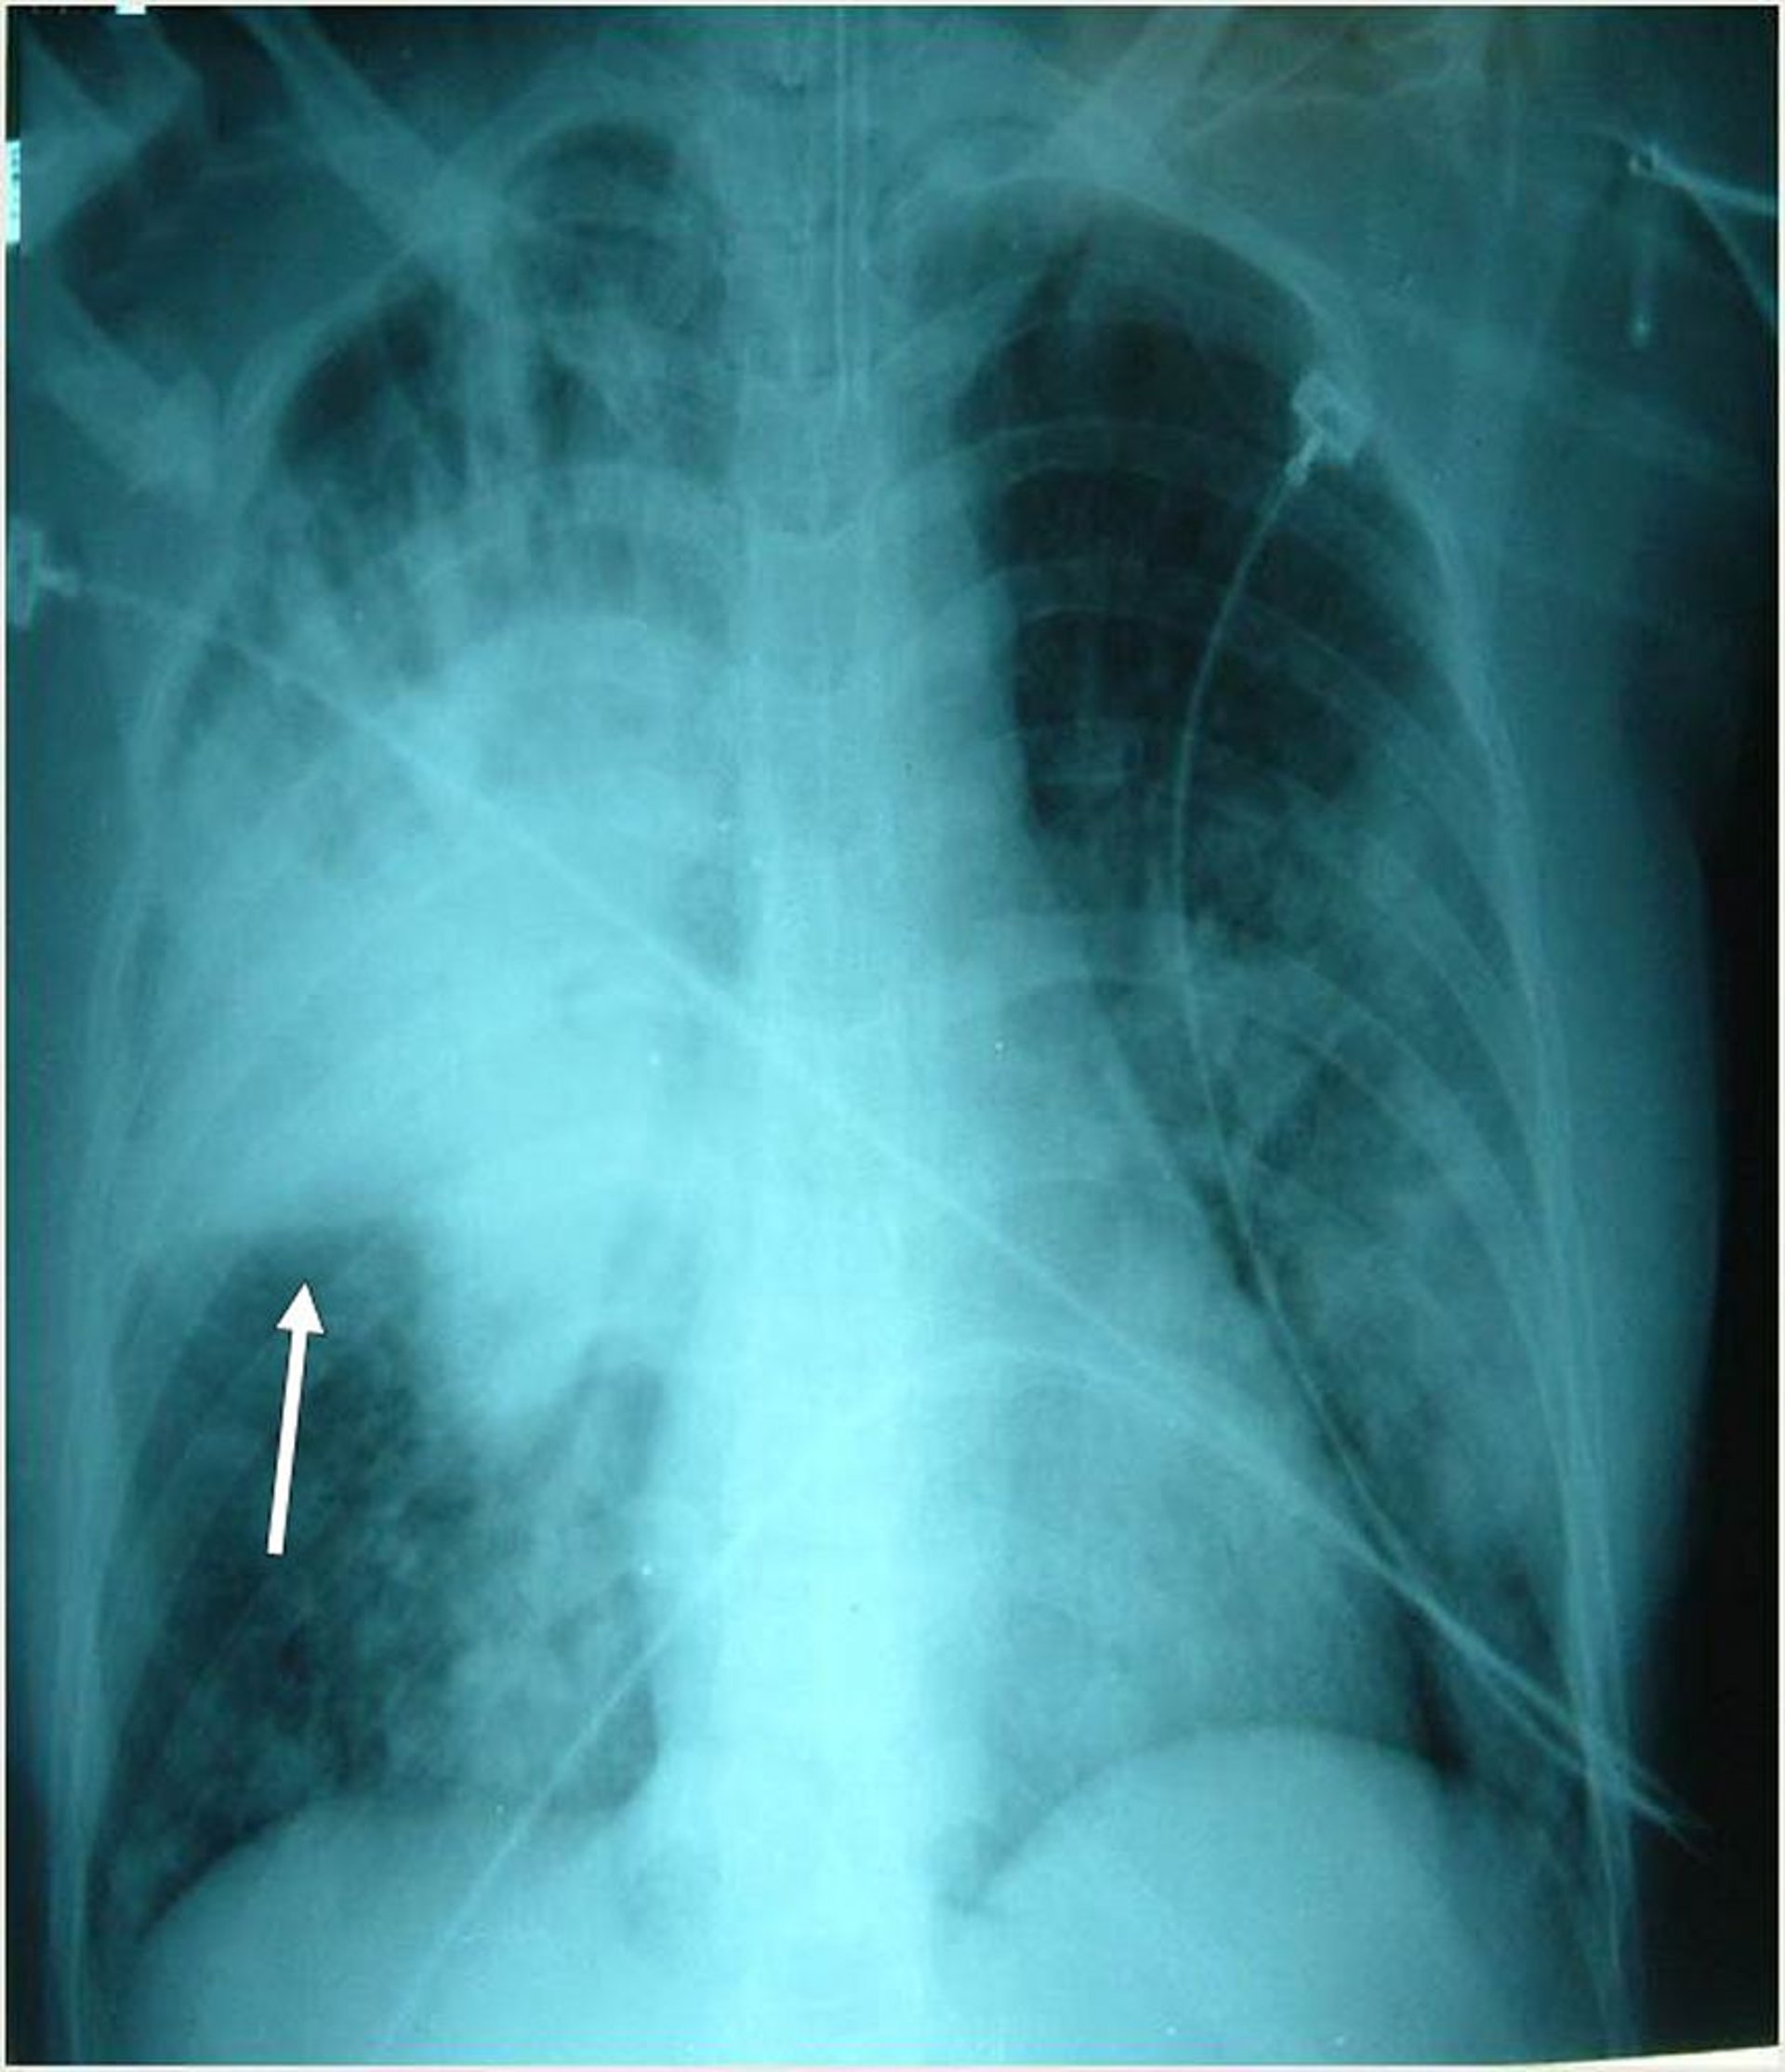

Neumonía severa

Este paciente intubado tiene múltiples infiltrados bilaterales, más prominentemente en el lóbulo superior derecho. La flecha indica la fisura horizontal derecha.

Photo courtesy of Thomas M. File, Jr., MD MSc MACP FIDSA FCCP.